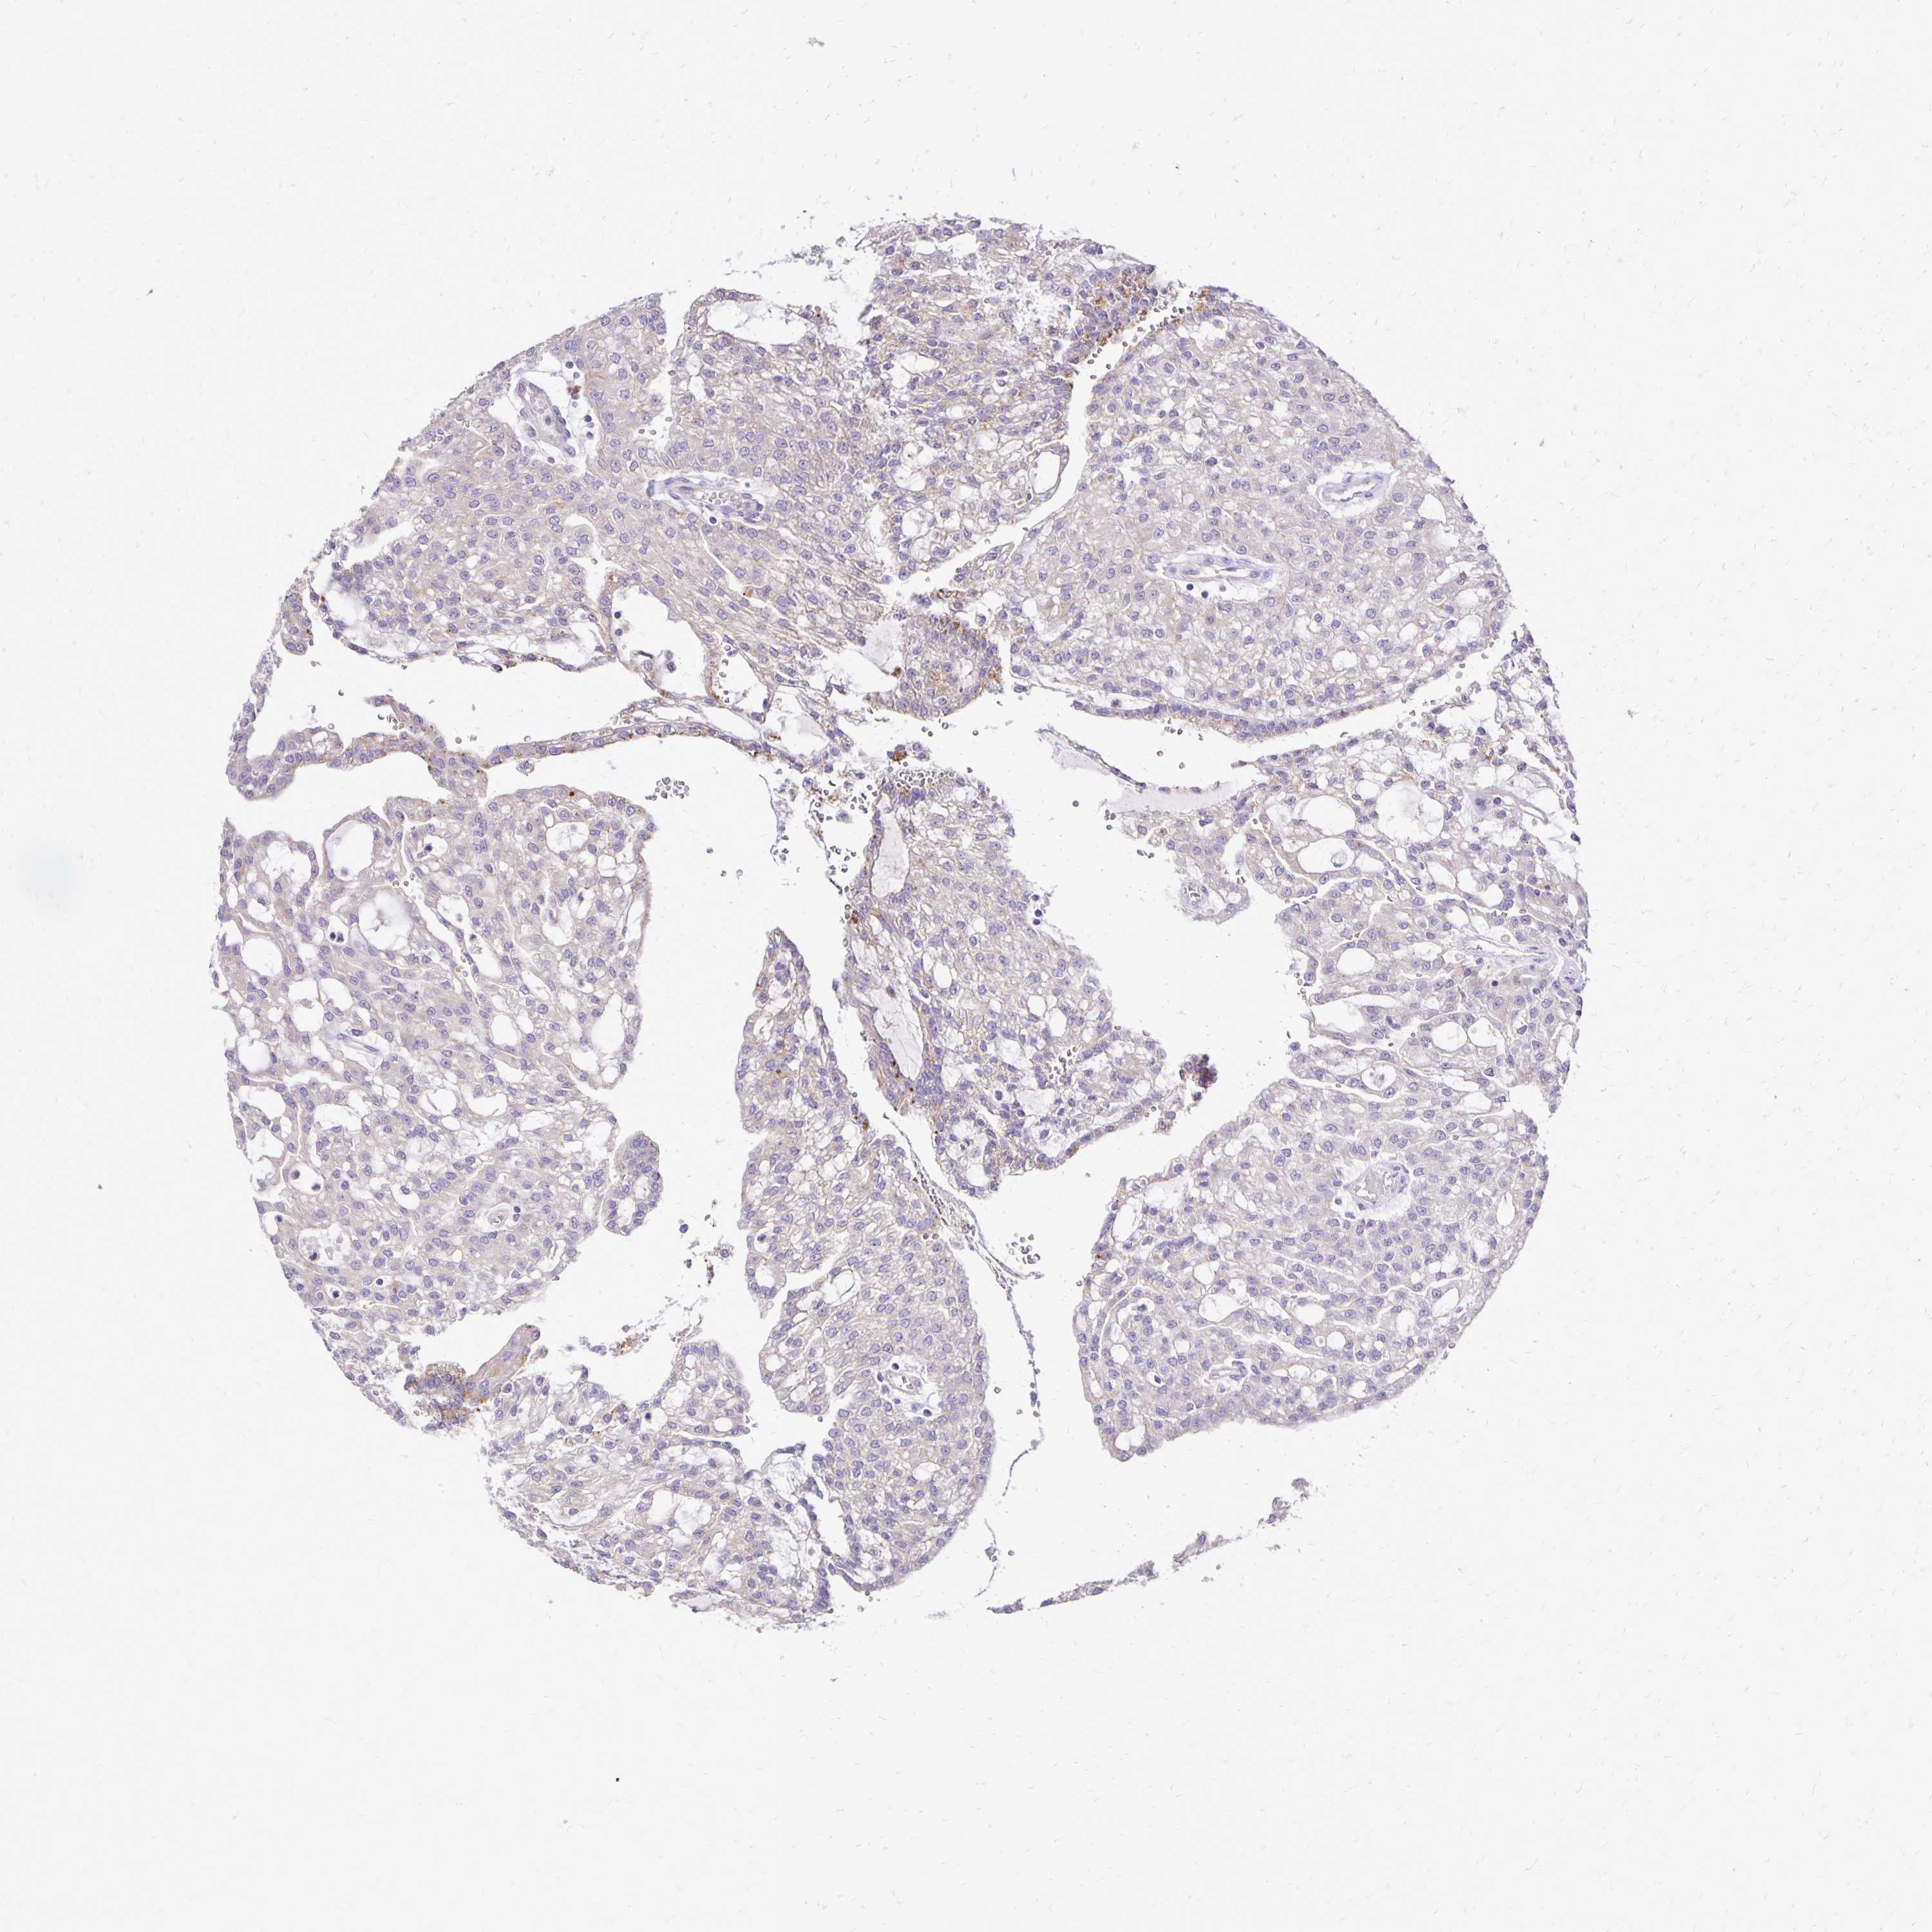

KIDNEY RENAL CLEAR CELL CARCINOMA (VALIDATION) - Interactive survival scatter ploti

The Survival Scatter plot shows the clinical status (i.e. dead or alive) for all individuals in the patient cohort, based on the same data that underlies the corresponding Kaplan-Meier plots. Patients that are alive at last time for follow-up are shown in blue and patients who have died during the study are shown in red.

The x-axis shows the expression levels (FPKM) of the investigated gene in the tumor tissue at the time of diagnosis. The y-axis shows the follow-up time after diagnosis (years). Both axes are complimented with kernel density curves demonstrating the data density over the axes. The top density plot shows the expression levels (FPKM) distribution among dead (red) and alive patients (blue). The right density plot shows the data density of the survived years of dead patients with high and low expression levels respectively, stratified using the cutoff indicated by the vertical dashed line through the Survival Scatter plot. This cutoff is automatically defined based on the FPKM cutoff that minimizes the p-score. The cutoff can be changed by dragging the vertical line or by entering a cutoff value in the square labeled "Current cut-off".

Under the Survival Scatter plot the p-score landscape (black curve; left axis) is shown together with dead median separation (red curve; right axis). Dead median separation is the difference in median mRNA expression between patients who have died with high and low expression, respectively. It is calculated as follows: median FPKM expression of dead patients with high expression - median FPKM expression of dead patients with low expression. This is intended to aid the user in visually exploring custom cutoffs and the associated p-scores and dead median separation.

Individual patient data is displayed and can be filtered by clicking on one or more of the category buttons on the top of the page. Categories describing expression level and patient information include: high, low, alive, dead, female, male and tumor stages. The scale of the x-axis can be toggled between linear and log-scale by clicking on the "x log" button. Mouse-over function shows TCGA ID, patient information and mRNA expression (FPKM) for each patient.

& Survival analysisi

Kaplan-Meier plots summarize results from analysis of correlation between mRNA expression level and patient survival. Patients were divided based on level of expression into one of the two groups "low" (under cut off) or "high" (over cut off). X-axis shows time for survival (years) and y-axis shows the probability of survival, where 1.0 corresponds to 100 percent.

EIF5A is validated prognostic, high expression is unfavorable in Kidney Renal Clear Cell Carcinoma (validation)

Best expression cut offi

Based on the FPKM value of each gene, patients were classified into two groups and association between prognosis (survival) and gene expression (FPKM) was examined. The best expression cut-off refers the FPKM value that yields maximal difference with regard to survival between the two groups at the lowest log-rank P-value. Best expression cut-off was selected based on survival analysis .

When clicking on this number, the vertical dashed line indicating cut-off, the interactive survival plot, and the Kaplan-Meier curve will be adjusted to show results based on the best expression cut-off.

: 160.56

TCGA RNA samplesi

RNA-seq data is reported as average FPKM (number Fragments Per Kilobase of exon per Million reads), generated by the The Cancer Genome Atlas (TCGA) .

Normal distribution across the dataset is visualized with box plots, shown as median and 25th and 75th percentiles. Points are displayed as outliers if they are above or below 1.5 times the interquartile range. FPKM values of the individual samples are presented next to the box plot.

Average pTPM 141.1

Number of samples 100